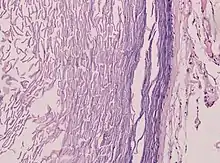

Histopathology, showing a keratinizing stratified squamous epithelium, and a lumen containing keratin flakes

Histopathology showing epithelium and lamellated keratin (left)